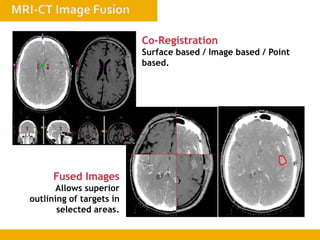

Co-Registration

Surface based / Image based / Point

based.

Fused Images

Allows superior

outlining of targets in

selected areas.